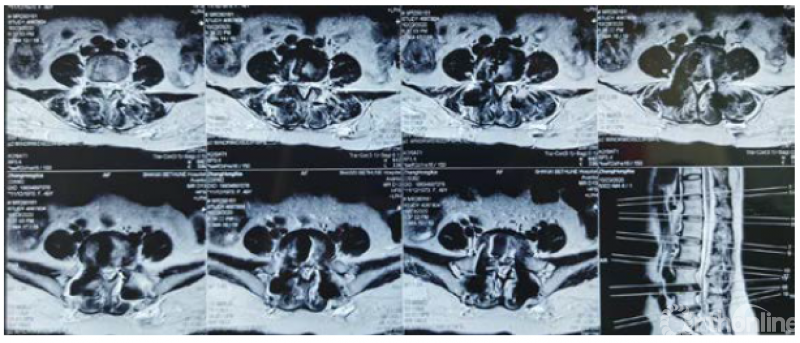

病例分享:(滑动查看)